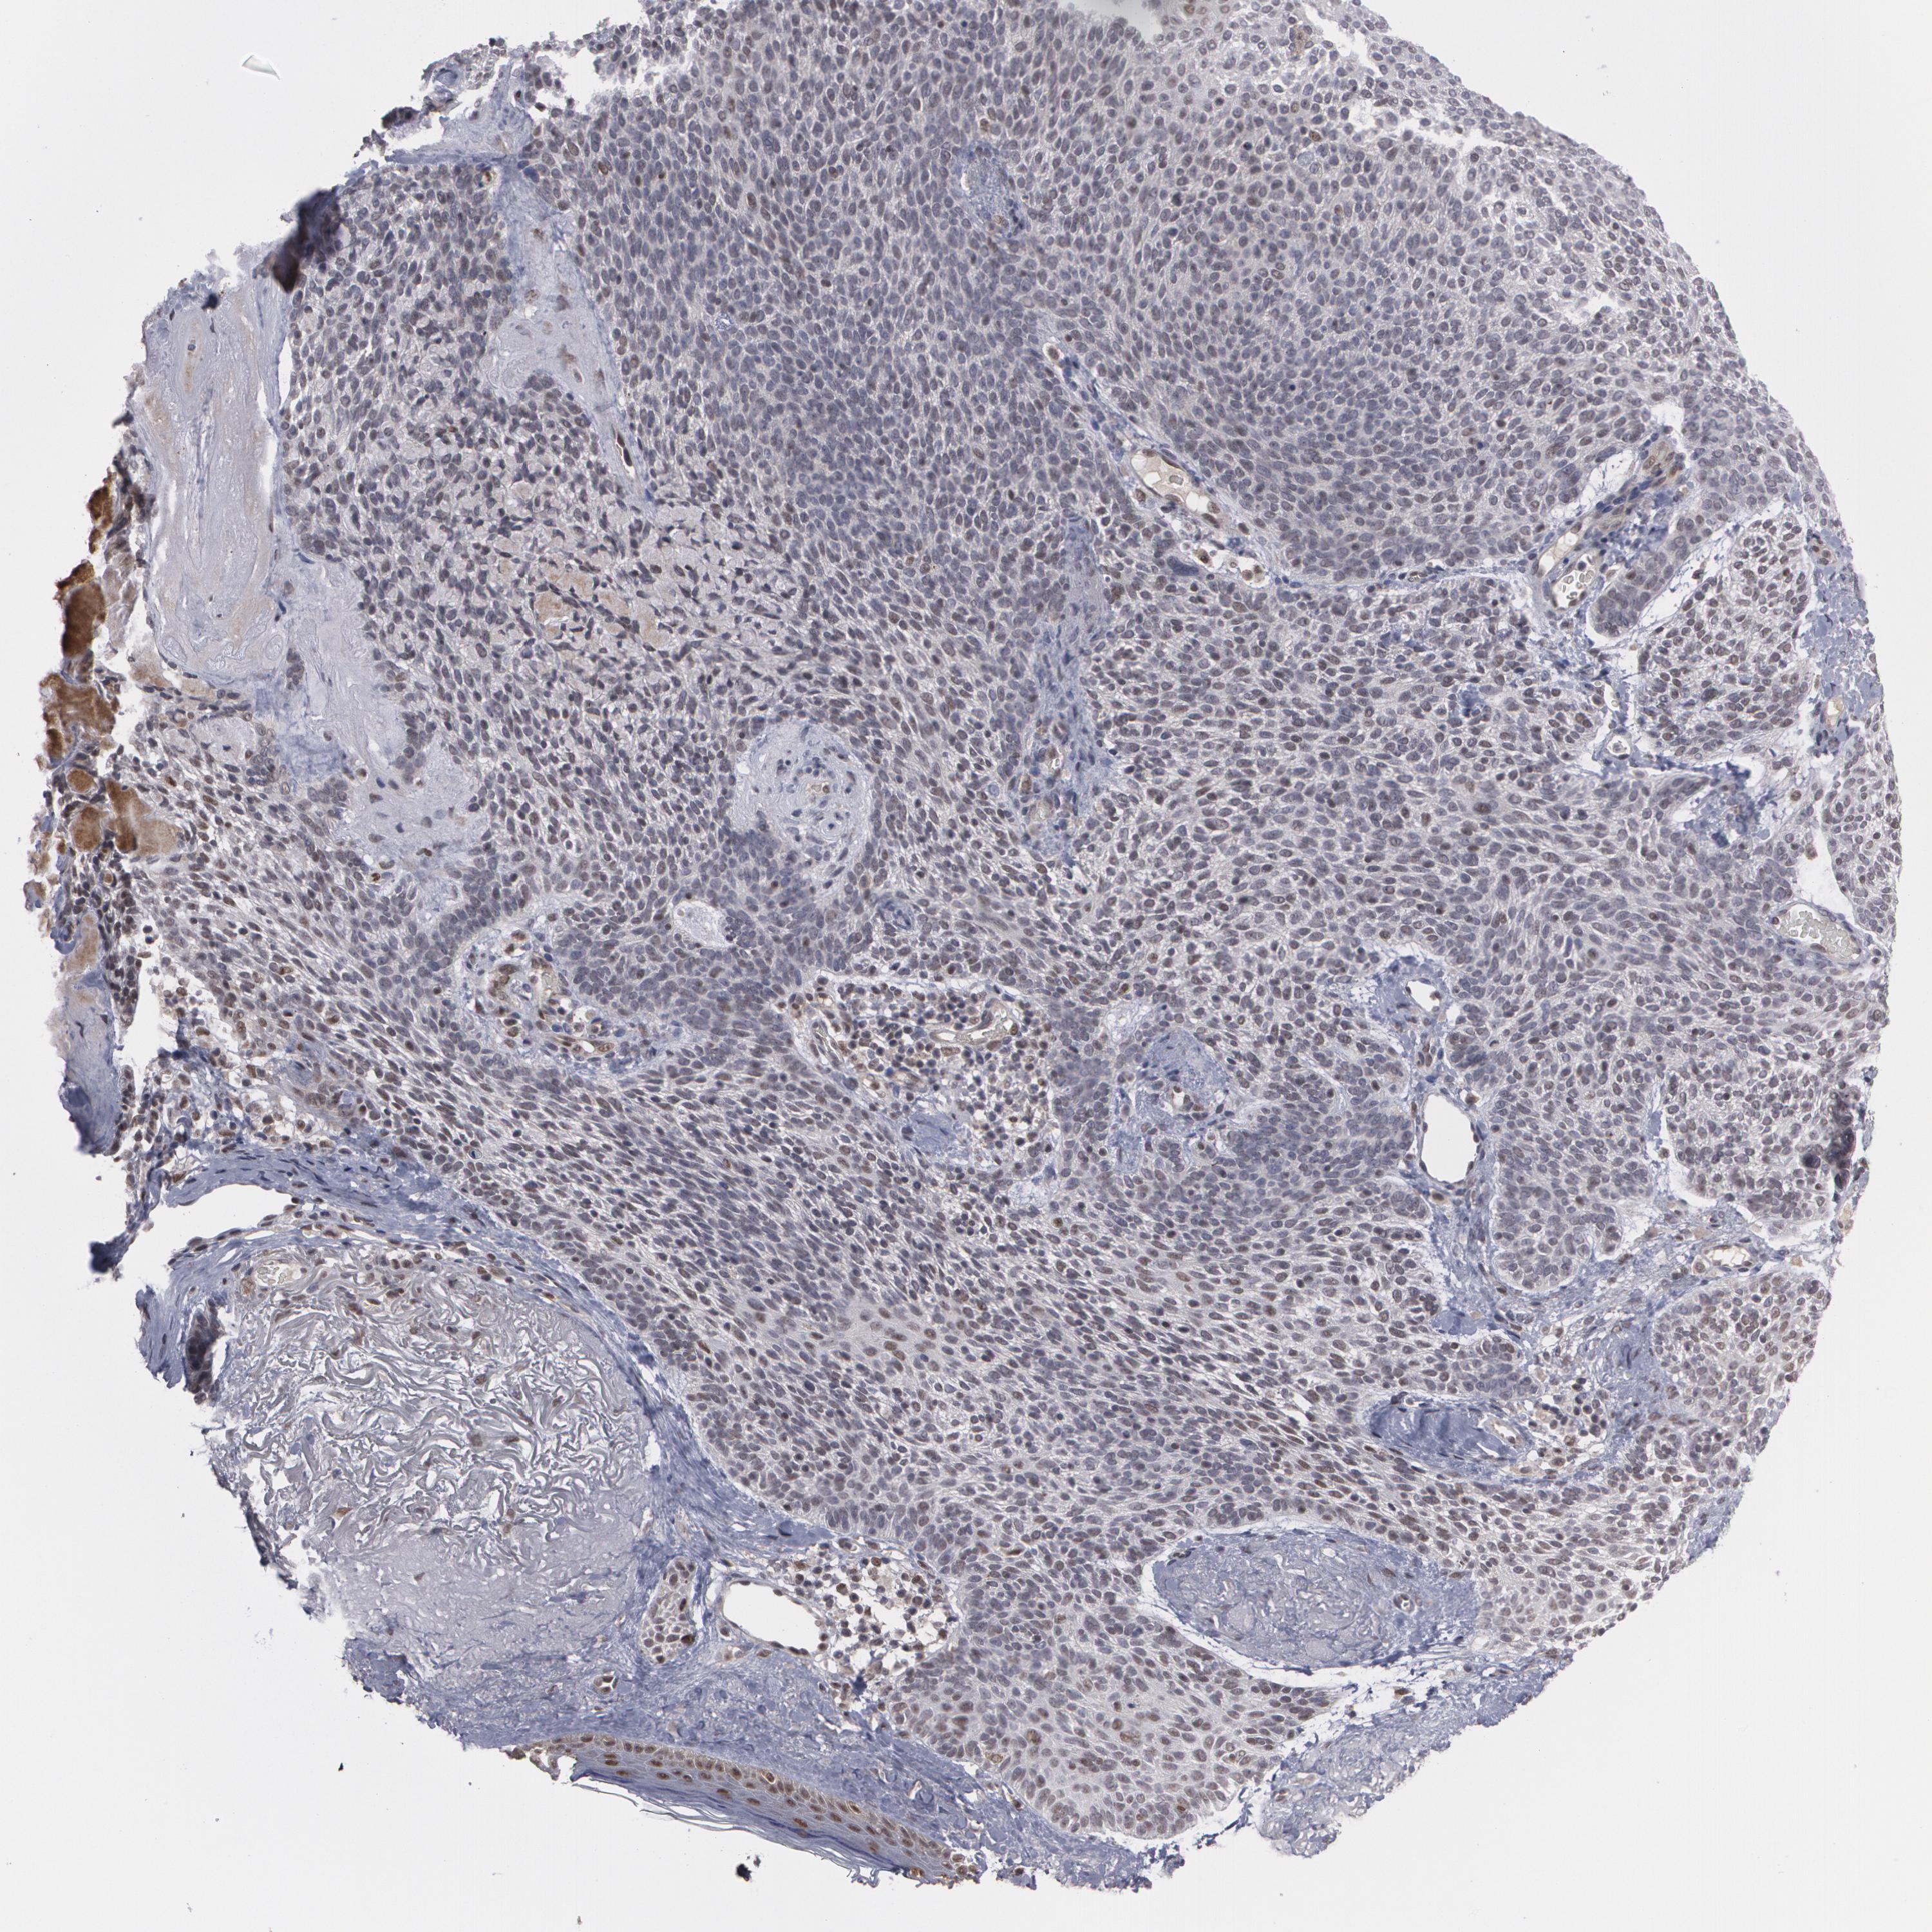

CANCER SKIN CANCER Show tissue menu

SKIN CANCER - Protein expressioni

A mouse-over function shows sample information and annotation data. Click on an image to view it in a full screen mode. Samples can be filtered based on level of antibody staining by selecting one or several of the following categories: high, medium, low and not detected. The assay and annotation is described here.

Each image is clickable and will lead to virtual microscopy that enables deeper exploration of all samples and also displays staining intensity scores, fraction scores and subcellular localization as well as patient and tissue information for each sample.

Antibody HPA001846

Basal cell carcinoma